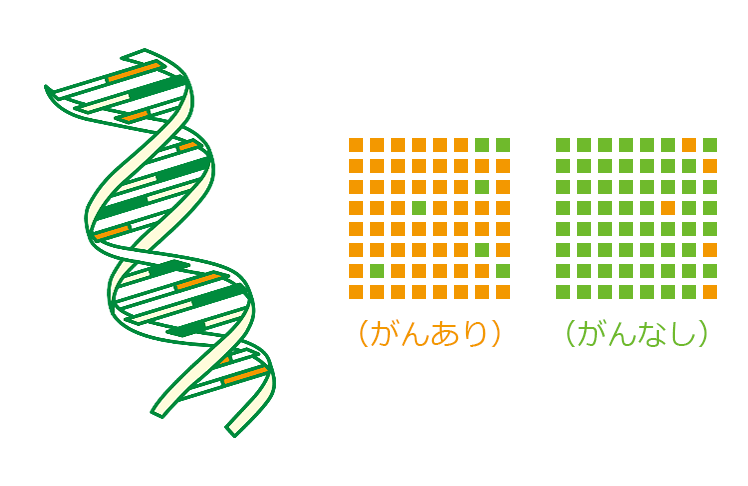

マイクロアレイ血液検査(消化器系癌血液検査)

マイクロアレイ血液検査は、消化器系癌(胃癌、大腸癌、膵臓癌、胆道癌)の検出を血液検査(採血量は約5ml)で行います。遺伝子解析で癌細胞の増殖に伴う異常な遺伝子の発現を見つけ出すことで、画像検査で検出できないような早期の段階の消化器癌の有無を調べることができます。内視鏡検査が苦手な方や膵臓や胆道の検査を行いたい方におすすめいたします。